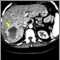

Hemangioma - CT scan